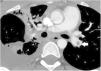

Case 2. Female adolescent aged 14 years with morbid obesity (weight, 115kg; BMI, 38) assessed in the emergency department for dyspnea of abrupt onset associated with chest pain and syncope. She had tachycardia (160bpm) with an arterial blood pressure at the limit of normal for age (105/50) and did not require vasoactive drugs. The relevant recent history was having been bedridden the previous week due to a knee sprain without receiving antithrombotic prophylaxis, leading to development of DVT in the left popliteal vein. The salient findings of blood tests were a D-dimer level of 13 700ng/mL and elevation of troponin levels to up to 506ng/L and of pro-B-type natriuretic peptide to 589pg/mL. The CT angiogram confirmed bilateral PE (Fig. 2) with signs of right ventricular (RV) overload, which was also assessed by means of echocardiography (tricuspid annular plane systolic excursion [TAPSE], 1.6cm; normal range, 1.9–2.7cm). She was transferred to our PICU, where treatment was initiated with unfractionated heparin (UFH) for anticoagulation and recombinant tissue plasminogen activator (rtPA) at a dose of 25mg for thrombolysis, with progressive clinical improvement over the next 24h. Intravenous infusion of UFH was maintained for four days (adjusting the dose as needed to maintain anti-Xa levels in the 0.3–0.7U/mL range) and subsequently switched to subcutaneous HBPM for three weeks followed by acenocoumarol for 6 months, maintaining the international normalized ratio (INR) between 2 and 3. The follow-up CT scan showed resolution after completion of treatment.